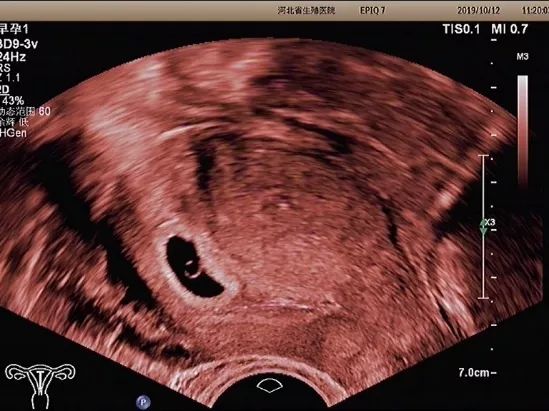

孕早期超声检查的内容

孕早期超声检查的内容主要有

以下5个方面

妊娠囊

确定妊娠囊是否在宫腔内,妊娠囊在宫腔内的位置、数目及大小。妊娠囊的大小可随孕周增长而增长。

卵黄囊

卵黄囊是妊娠囊内超声能发现的第一个解剖结构。当超声发现卵黄囊,即可以确定妊娠。正常的卵黄囊直径约3~8mm,卵黄囊过大、过小或不显示及变形均提示妊娠结局不良。

胚芽

可根据胚芽长度评估孕周,有无心管搏动,确定胚胎是否存活。

经阴道超声检查

经阴道超声检

查又称腔内超声

孕妇取膀胱截石位

在腔内超声探头上

套上无菌避孕套

将探头伸入阴道进行检查

经阴道超声有哪些优势呢?

优势一

经阴道超声检查发现

妊娠囊、卵黄囊的时间

早于经腹部超声

常能发现经腹部超声

不能发现的宫内早早孕和异位妊娠

优势二

经阴道超声具有

无需充盈膀胱

分辨率高、图像清晰的优势

对于早孕期不能憋尿、肠道气体较多

腹壁脂肪层较厚的孕妇

阴道超声检查较腹部检查更具优势